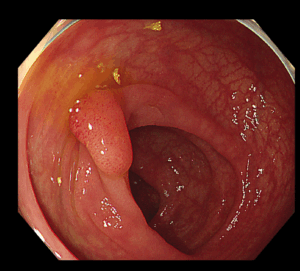

腸の粘膜の一部がイボ状に隆起したものを大腸ポリープといいます。大腸ポリープは組織の違いにより腫瘍性ポリープと非腫瘍性ポリープに大きく分けられ、腫瘍性ポリープはさらに悪性腫瘍(がん)と良性腫瘍(腺腫)に分けられます。

大腸がんができる過程としては、多くの場合は良性腫瘍(腺腫)が悪性化してがんになるため、腺腫を切除(ほとんどは大腸内視鏡で切除可能です)すれば大腸がんになりにくくなると考えられています。

大腸内視鏡検査にてポリープを発見した場合、拡大観察を行い、そのポリープが将来がんになりやすいポリープかどうか判断します。その結果切除が必要と判断された場合には、可能な限り当日ポリープ切除を行います。ポリープが大きい場合、入院して切除が必要な場合、外科的に手術が必要な場合は無理して切除を行わず、安心して治療ができる大きな病院へ紹介する場合もあります。またポリープが多数ある場合は何回かに分けて切除することもあります。